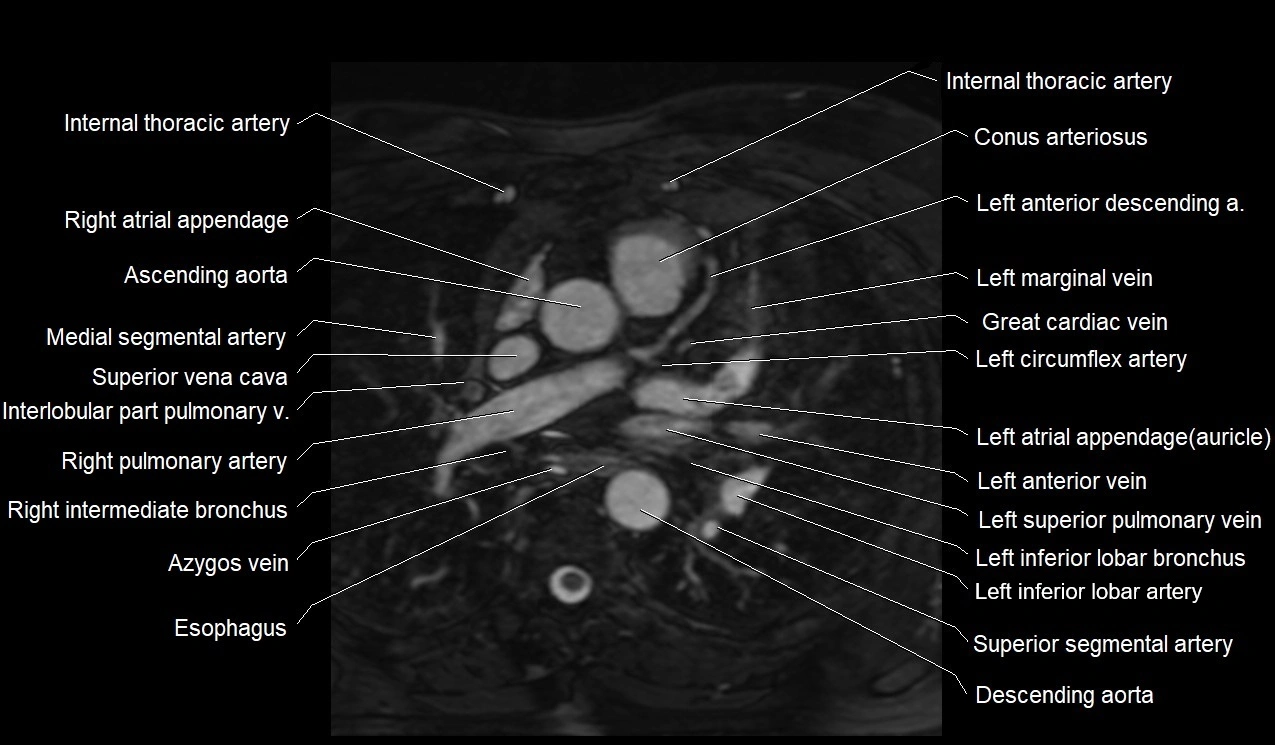

MRI image